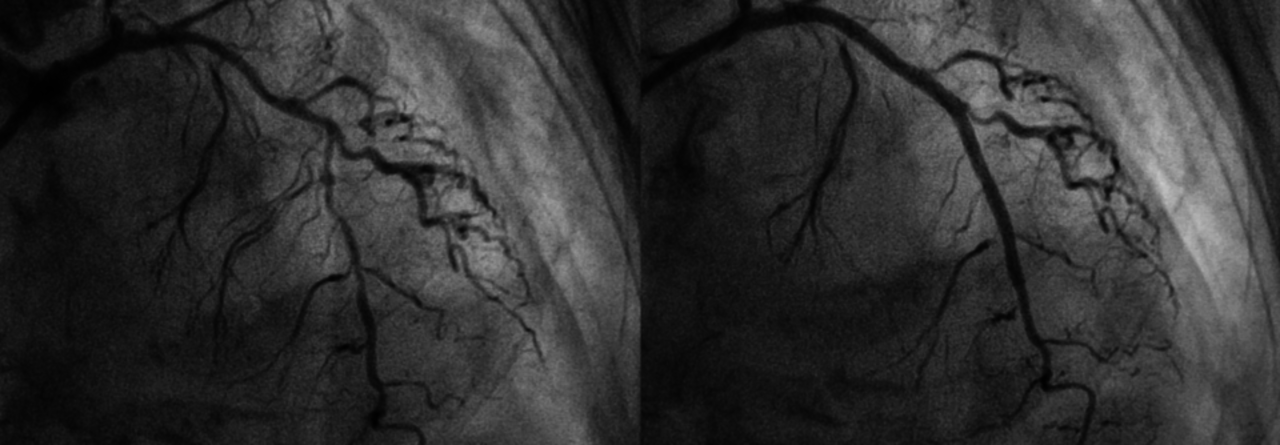

Nach der Implantation eines modernen medikamentenfreisetzenden Stents (hier im vorderen, absteigenden Ast der linken Koronararterie) kann die Dauer der dualen Plättchenhemmung deutlich verkürzt werden. Nach der Implantation eines modernen medikamentenfreisetzenden Stents (hier im vorderen, absteigenden Ast der linken Koronararterie) kann die Dauer der dualen Plättchenhemmung deutlich verkürzt werden. © Ploypilin – stock.adobe.com

Eine weitere Möglichkeit zur Deeskalation setzt bei den Stents an: Moderne medikamentenfreisetzende Modelle (Drug-eluting-Stents; DES) erlauben eine deutliche Verkürzung der DAPT und werden deshalb inzwischen auch für ältere Patienten präferiert. Ihre Vorteile gegenüber Metallstents konnten diverse Untersuchungen zeigen. Eine davon ist die ­SE­NIOR-Studie mit Patienten ≥ 75 Jahre, die nach der Implantation eines resorbierbaren Polymer-DES einen Monat (bei Patienten mit chronischem Koronarsyndrom; CCS) oder ein halbes Jahr (Patienten mit ACS) dual behandelt wurden. Gesamtmortalität, Infarktrate und erneute Revaskularisationen des Zielgefäßes waren verringert mit DES verglichen mit Metallstents (Risk Ratio 0,71) ohne vermehrte Hämorrhagien. Eine andere Arbeit ermittelte für ein oder drei Monate der dualen Plättchenhemmung sogar eine deutliche Reduktion schwerer Blutungen.